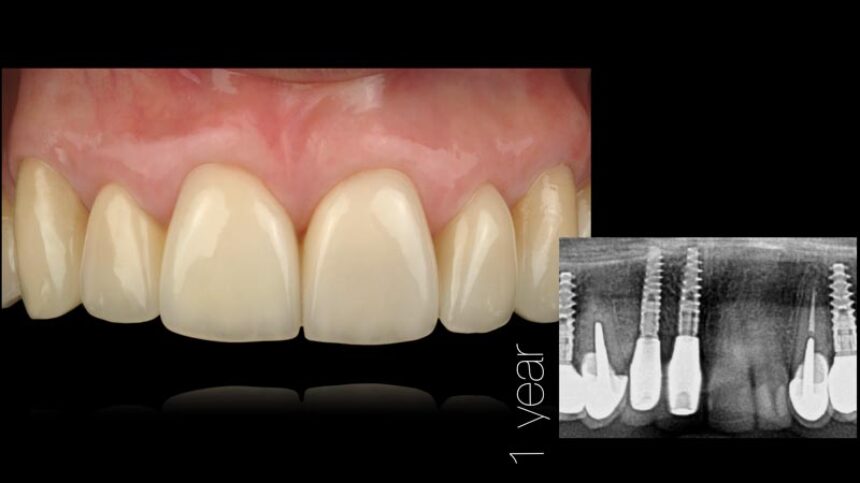

Την διημερίδα θα πλαισιώσει επίσης ο Dr. Iñaki Gamborena εστιάζοντας τις ομιλίες του στους σημαντικούς εκείνους παράγοντες που επηρεάζουν την επιτυχία της θεραπείας στην αισθητική ζώνη τόσο σε ασθενείς με αμιγώς οδοντικό φραγμό, αλλά και εμφυτευματικές αποκαταστάσεις. Οι παρουσιάσεις του θα περιέχουν τη χειρουργική, αλλά και την προσθετική αντιμετώπιση των περιστατικών αυτών και επίσης και αυτός θα επεκταθεί στη διαχείριση πολύπλοκων περιστατικών που έχουν αποτύχει στο παρελθόν.

Αισθητική Οδοντιατρική με Εμφυτεύματα – βασικά επιστημονικά στοιχεία

Ανατομικοί παράγοντες με καθοριστικό ρόλο στην αισθητική αποκατάσταση επί εμφυτευμάτων – Διάγνωση και σχεδιασμός θεραπείας.

Διαχείριση μαλακών ιστών.

Χειρουργικές τεχνικές για την αύξηση των σκληρών και των μαλακών ιστών.